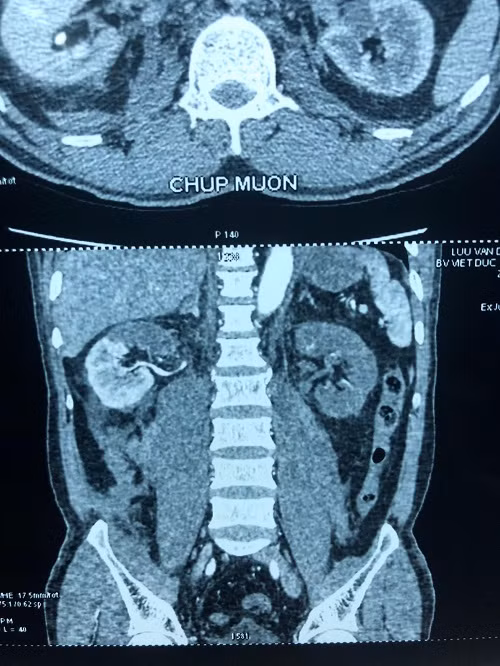

Flim trước mổ của người bệnh, thận phải mất 1/2 chức năng, thận trái mất hoàn toàn chức năng.

Tại đây, kết quả chụp chiếu phát hiện thận bên phải có huyết khối động mạch cực trên, mất phần cấp máu cho cực trên, thận bên trái thiếu máu hoàn toàn, chức năng thận giảm, có biểu hiện suy thận.